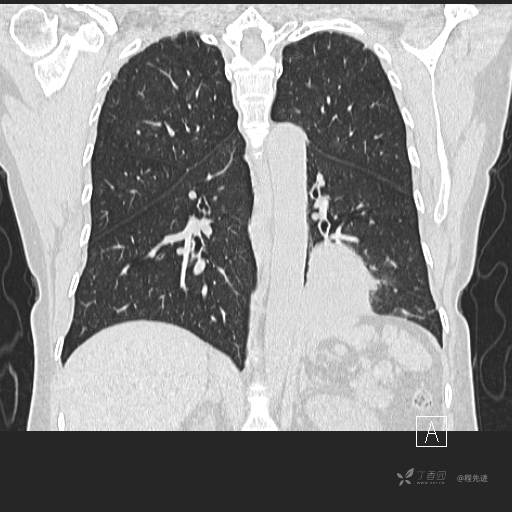

冠状位重建

CT值:平扫:31HU,动脉期:74HU,静脉期:84HU